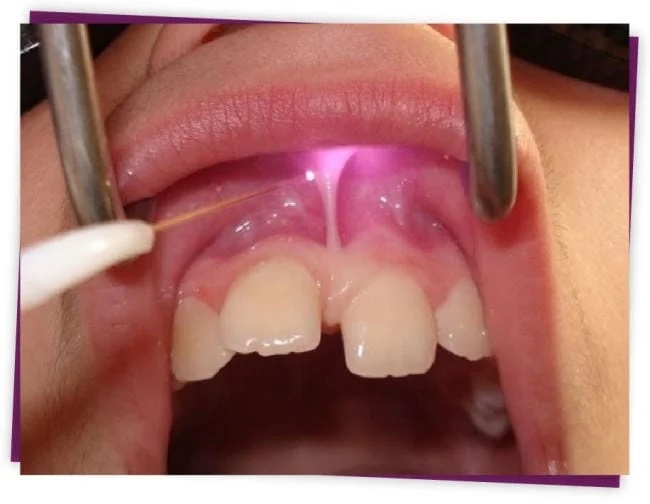

Thắng môi bám thấp

Bình thường thắng môi bám vào gianh giới giữa phần nướu di động và cố định. Tuy nhiên nhiều trường hợp thắng môi bám đến sát nhú nướu hoặc vượt qua nhú nướu vào mặt trong của xương hàm. Trường hợp này được gọi là thắng môi bám thấp. Nếu không được phát hiện sớm và điều trị kịp thời sẽ dẫn đến các vấn đề như:

Can thiệp phẫu thuật là phương pháp tốt nhất để giúp môi, má, lưỡi cử động bình thường. Các thắng này có thể được cắt bằng lưỡi dao mổ hoặc phẫu thuật bằng tia laser dưới tiêm tê hoặc gây mê tuỳ theo độ tuổi và sự hợp tác của bệnh nhân. Nói chung đây là phẫu thuật đơn giản, không nguy hiểm và hầu như không đau. Bệnh nhân hồi phục nhanh sau phẫu thuật.

Dùng Laser để cắt thắng môi